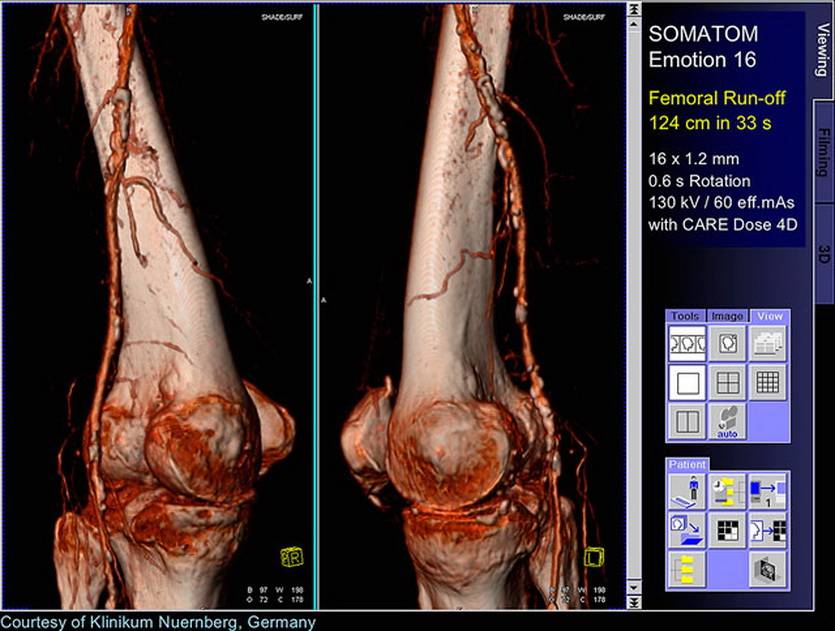

Томография позволяет строить сложные трехмерные модели

Если аномалия на рентгене может спрятаться за чем-то другим, поглощающим рентгеновское излучение лучше (так «исчезают» за костями многие опухоли), от КТ ей не убежать: специалист может повернуть изображение нужной стороной.

Точно так же с помощью трехмерного изображения оценивают состояние сложных поверхностей, практически неидентифицируемых на рентгене. Например, не только размеры, но и форму органов со всех сторон.

Что ещё интереснее, с помощью современных аппаратов для КТ с высокой скоростью генерации пучков излучения можно получить изображение в динамике. Посмотреть не только что, но и как.

Кровеносную систему в динамике иначе не увидеть